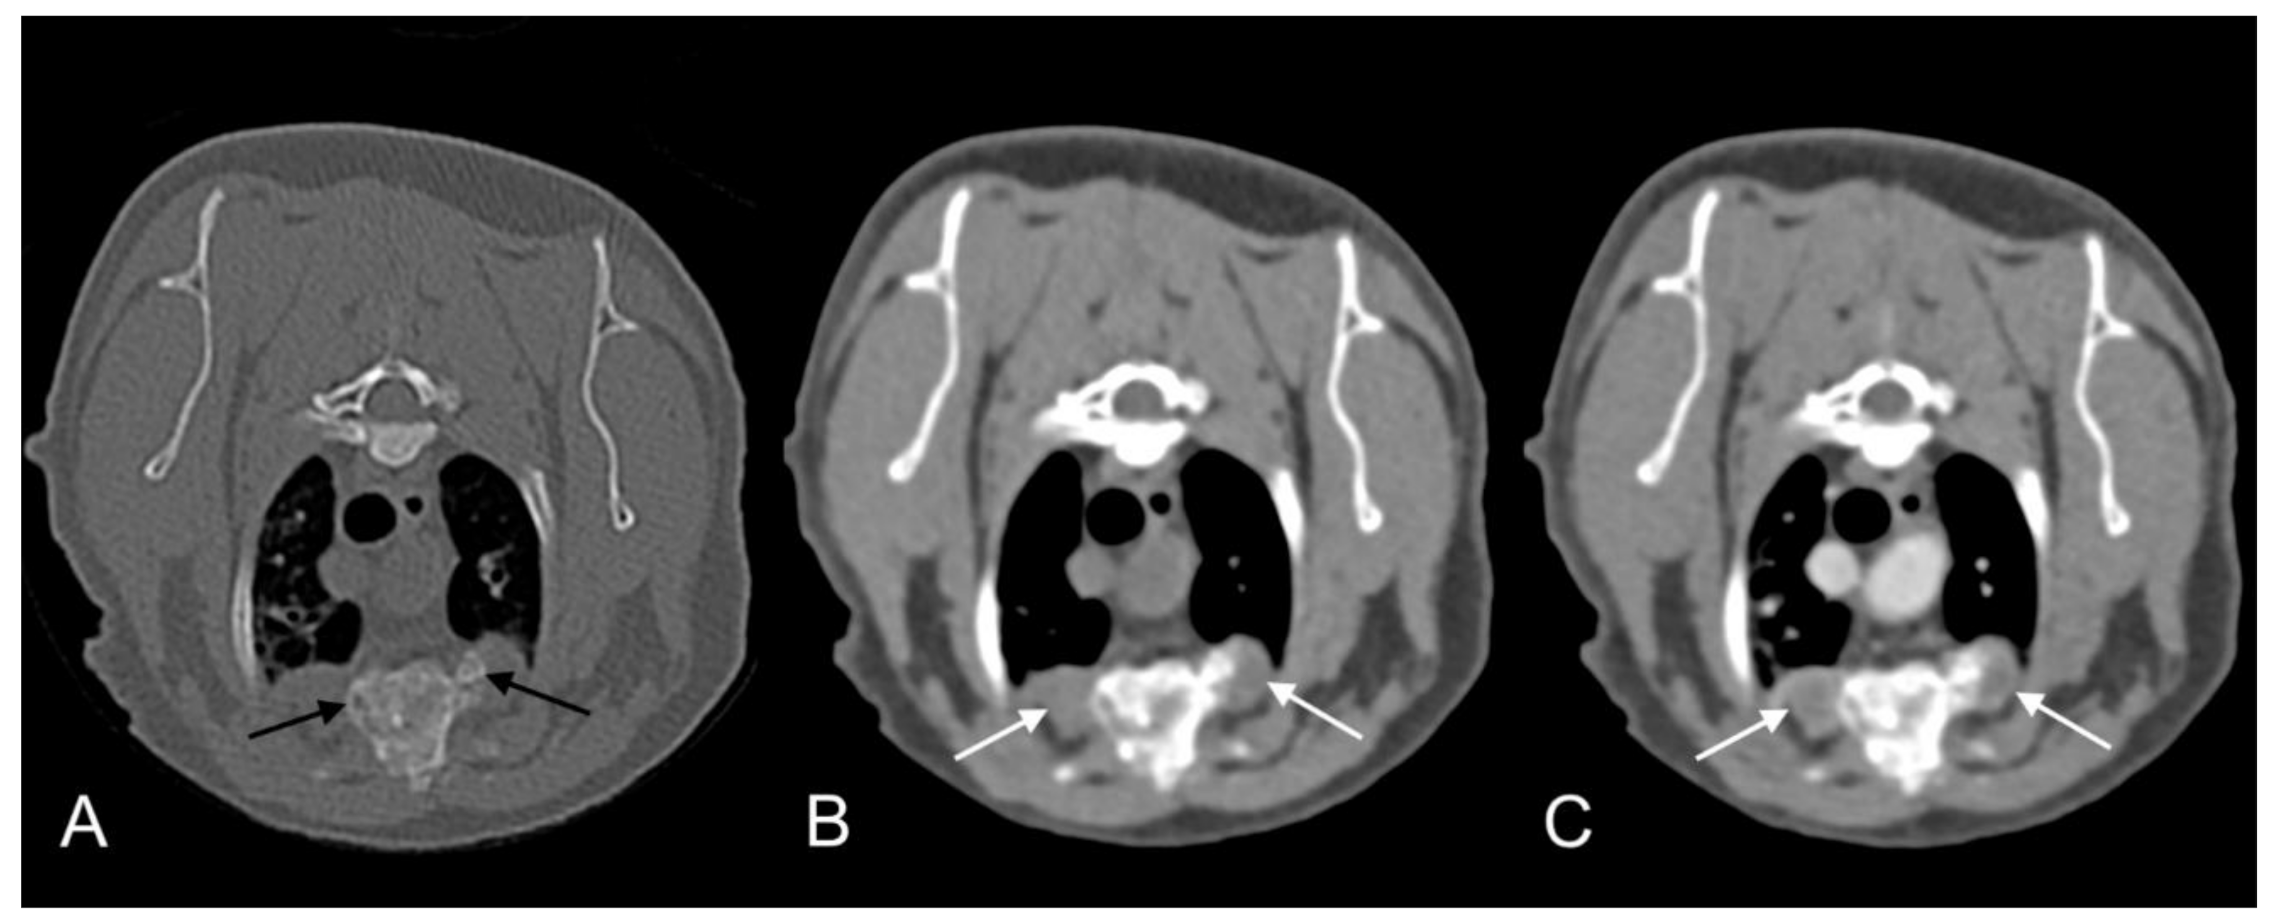

- Bennett, A.D.; Lalor, S.; Schwarz, T.; Gunn-Moore, D.A. Radiographic findings in cats with mycobacterial infections. J. Feline Med. Surg. 2011, 13, 718–724. [Google Scholar] [CrossRef] [PubMed]

- Major, A.; Holmes, A.; Warren-Smith, C.; Lalor, S.; Littler, R.; Schwarz, T.; Gunn-Moore, D. Computed tomographic findings in cats with mycobacterial infection. J. Feline Med. Surg. 2016, 18, 510–517. [Google Scholar] [CrossRef]

- Major, A.; O’Halloran, C.; Holmes, A.; Lalor, S.; Littler, R.; Spence, S.; Schwarz, T.; Gunn-Moore, D. Use of computed tomography imaging during long-term follow-up on nine feline tuberculosis cases. J. Feline Med. Surg. 2018, 20, 189–199. [Google Scholar] [CrossRef]